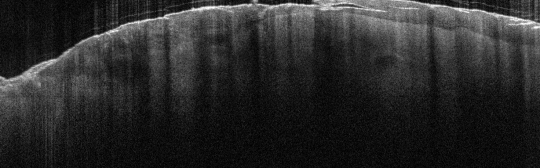

VA15: Right Dorsal Hand, Adjacent, Normal